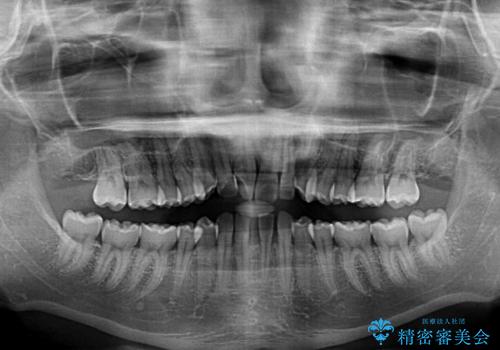

下顎前歯が2歯欠損しており、スペースになっており、上顎は叢生歯列となってしました。

奥歯の咬み合わせを考えると、理想的には2歯、最低でも1歯は下顎前歯の欠損部にインプラントやブリッジにより歯数を増やす必要がありました。

周囲の歯を削らないようにするためインプラントがおすすめとなりますが、歯根の移動が不十分な場合にはインプラントを埋入する幅が獲得できないため、その場合にはオールセラミックブリッジにより補綴治療を行うこととして、矯正治療を行うこととしました。

当初は上記計画でしたが、レントゲン撮影よりインプラント埋入は困難と判断され、患者様と相談の上、歯を削ってブリッジとするよりも、奥歯の咬み合わせを多少妥協することとなっても、スペースを閉じて仕上げていくこととしました。